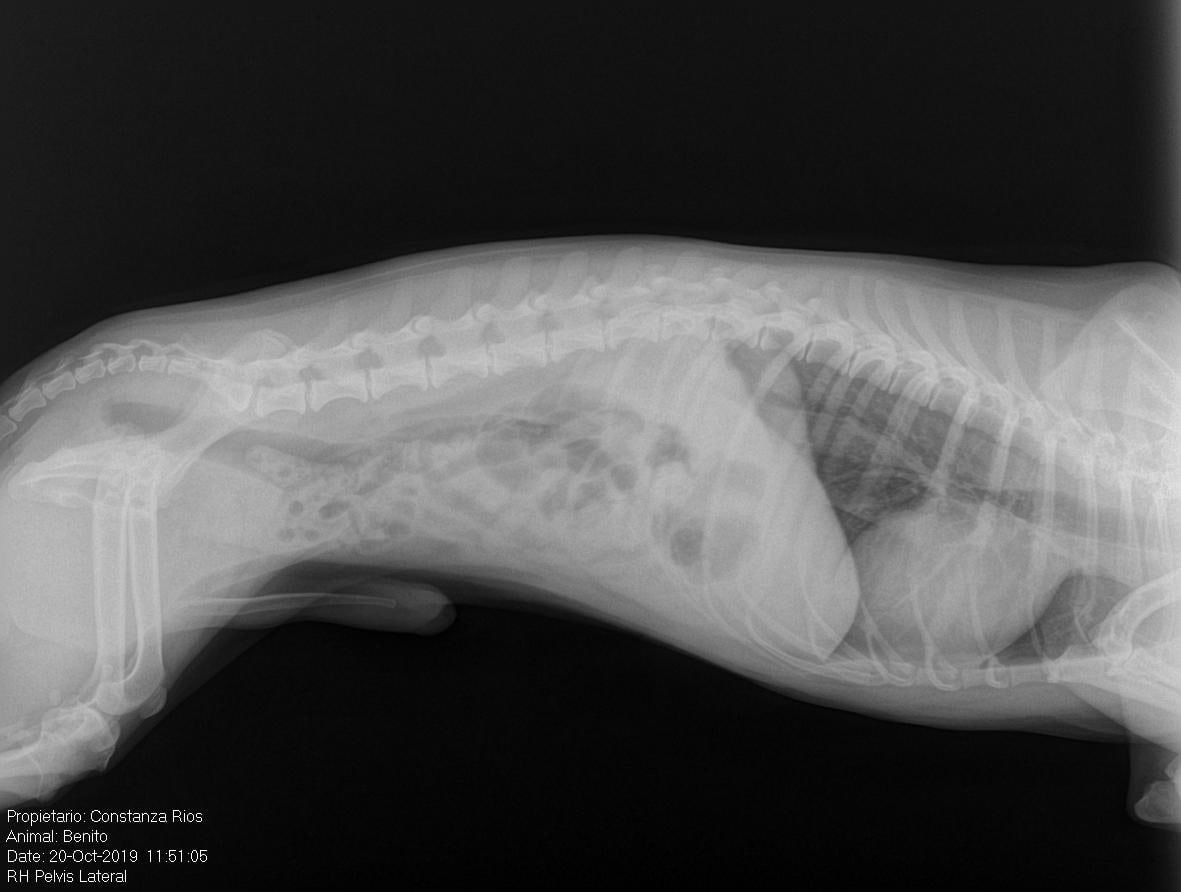

Pet's info: Dog | Maltipoo | Male | neutered | 6 years and 4 months old | 11 lbs

Hi, my dog has been suffering a back pain which I identified once I took him and he shouted. I took him to the vet and they gave him 3 days with anti-inflammatories but once the 3 days passed the pain came back. I took him to the vet again and they gave him 6 days with anti-inflammatories again. We are in day 5 and he has been relatively great but now the pain is coming back since he doesn't want to use the stairs for example. I will attach his x rays.

Poor Benito! When pets don't respond as well to anti-inflammaorties, I often try them on steroids (for 2-4 weeks), muscle relaxers and opioid pain medication. During this time, Benito should be crated at all times, allowed outside on a leash only to potty because you MUST make sure he is not moving around too much. You may also look into acupuncture or laser therapy which can also help significantly. Benito should be examined every 2 weeks until he is back to normal. The medications may need to be adjusted based upon his response. I hope this helps and that he feels better quickly.